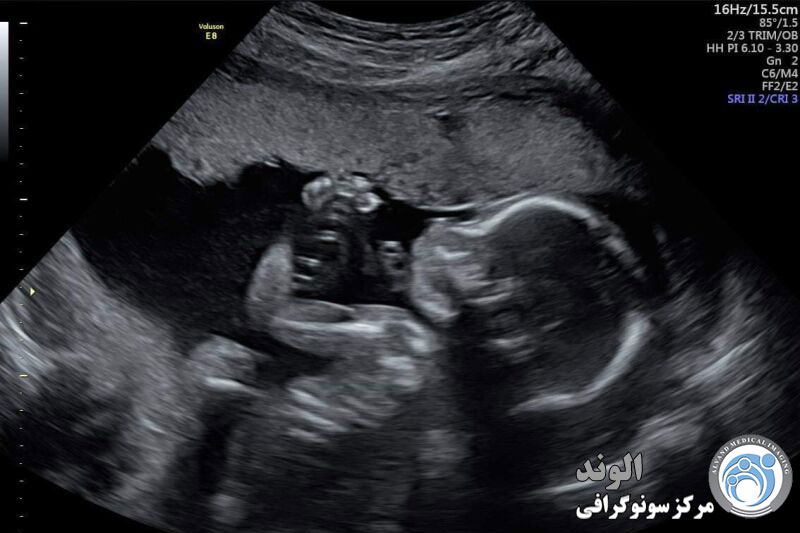

بررسی دقیق اسکن ناهنجاری

اندام های داخلی کودک شما به صورت مقطعی بررسی می شود که تشخیص آن ممکن است برای شما دشوار باشد. استخوانها سفید به نظر میرسند، مایع سیاه است و بافتهای نرم ممکن است درجات مختلف خاکستری به نظر برسند. در این زمان تغییراتی را در آناتومی طبیعی که ممکن است نشان دهنده یک ناهنجاری باشد را بررسی خواهیم کرد.

سر نوزاد از نظر شکل و اندازه بررسی می شود. سونوگرافی اندازه گیری های استاندارد را انجام می دهد و لب ها و بینی نوزاد را برای هر گونه نقص آشکار بررسی می کند.

کلیه ها، معده و مثانه نیز تصویربرداری می شوند. نوزاد تقریباً هر نیم ساعت یک بار دفع ادرار انجام می دهد، به همین دلیل مثانه در طی انجام اسکن پر و خالی می شود.

پاها، بازوها، دست ها و پاهای نوزاد بررسی می شود. بند ناف جنین جهت شمارش تعداد عروق مورد بررسی قرار می گیرد.

اندازهگیریهای معمولی که انجام میشوند عبارتند از: قطر دو جداره سر (BPD)، دور سر (HC)، دور شکم (AC) و طول استخوان ران (FL). این اندازه گیری ها دقتی در حدود یک تا دو هفته به اضافه یا منهای سن حاملگی واقعی نوزاد دارند. اگر اندازهگیریهای کودک شما در آن محدوده باشد، ما اندازهگیریها را طبیعی میدانیم.